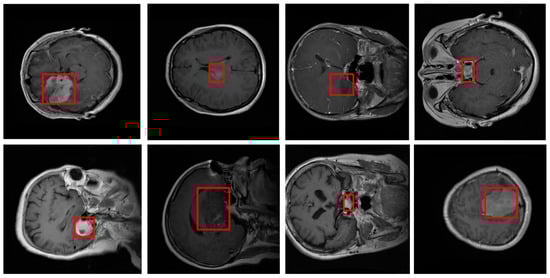

- We propose an innovative model that integrates spatial attention modules into the U-Net [4] architecture, allowing the network to focus on the most critical regions of MRI scans. This approach enables more precise and context-aware segmentation, particularly in delineating tumor boundaries where traditional U-Net [4] models may struggle due to noisy backgrounds or low-contrast regions.

- The spatial attention module selectively emphasizes informative areas within the feature maps, enhancing the model’s capability to capture subtle and complex patterns in tumor regions. This modification enhances the model’s accuracy in identifying fine-grained details essential for clinical diagnosis.

- Our model was evaluated on the Figshare dataset, which includes annotated MRI images of different brain tumor types: meningioma, glioma, and pituitary tumors. We provide a comprehensive comparison against leading segmentation models. Our results demonstrate that the proposed model achieves superior performance across metrics like accuracy, DSC, precision, and recall, confirming its robustness and reliability for clinical application.